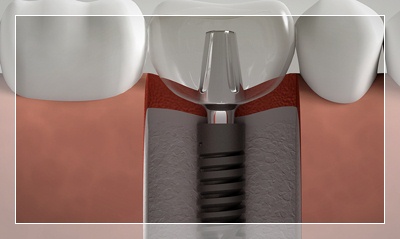

Diş Üstü ve İmplant Üstü Protezler

Ağızda mevcut olan doğal dişler ve/veya sağlam kökler üzerine doğrudan doğruya oturan ve takılıp çıkartılabilen total veya bölümlü protezlere Diş Üstü Protezler, retansiyon, destek ve stabilite sağlayabilmek için kısmen veya tamamen diş implantlarını kullanan protezlere İmplant Üstü Protezler adı verilir. İmplant üstü protezler sabit veya hareketli olabilirler.

İmplantoloji

Eksik dişleriniz için en modern ve kalıcı çözüm. Titanyum implantlarla doğal diş görünümü ve fonksiyonu. Çekmeköy'de deneyimli kadromuzla implant tedavisi.